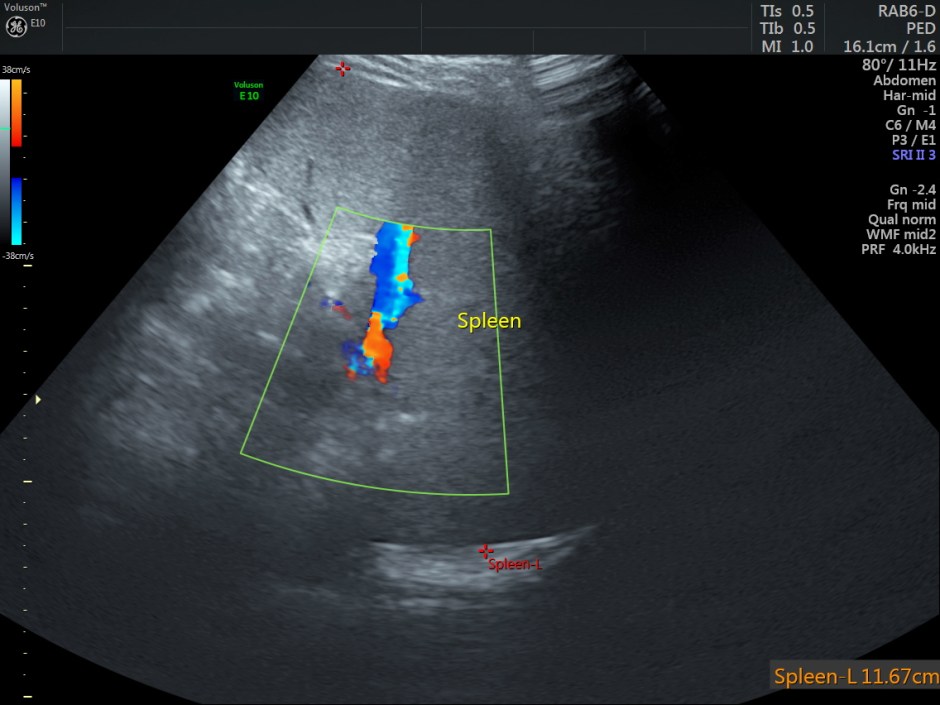

The scan revealed the following findings:

Mild splenomegaly

Other laboratory studies may be directed by history, physical examination, peripheral smear, and other laboratory findings. Ultrasonography is used to estimate the spleen size since the physical examination occasionally does not detect significant splenomegaly. Chest radiography, electrocardiography (ECG), and other studies are used to evaluate cardiopulmonary status.